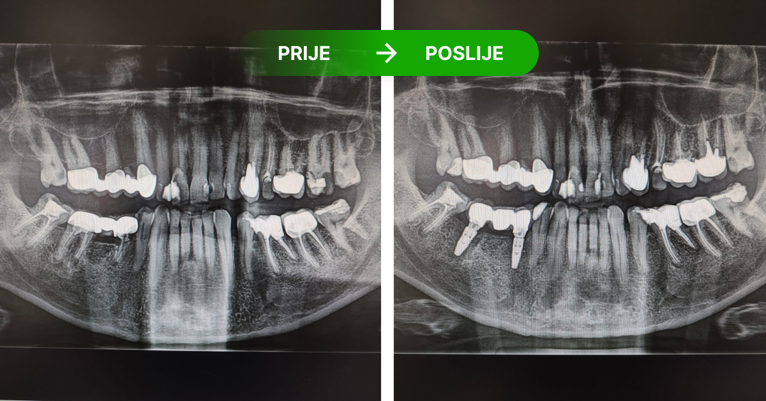

Zubni implantati su titanski vijci koji se ugrađuju u kost kao zamjena za korijen zuba, jednog ili više zuba. Pristup je individualan ovisno o RTG snimci i preostalom broju zuba. Nije potrebno brusiti susjedne zube, već ugrađujemo implantat. Ugrađujemo implantate Nobel Biocare. Ako se održava kvalitetna higijena i kontrola RTG snimanjem implantati traju doživotno, a njihovom ugradnjom zaustavlja se resporbcija kosti.

Dentalni implantati ugrađuju se u čeljust i njihovo učvršćivanje traje 3 do 4 mjeseca – kontrolira se rendgen slikom.

Postupak se izvodi u lokalnoj anesteziji i potpuno je bezbolan. Ukoliko je potrebo ugraditi više implantata, ugrađuju se istovremeno u jednoj posjeti. Nakon 3 do 4 mjeseca vrši se kontrola učvršćivanja i pristupa se izradi keramičkog mosta ili krunice.